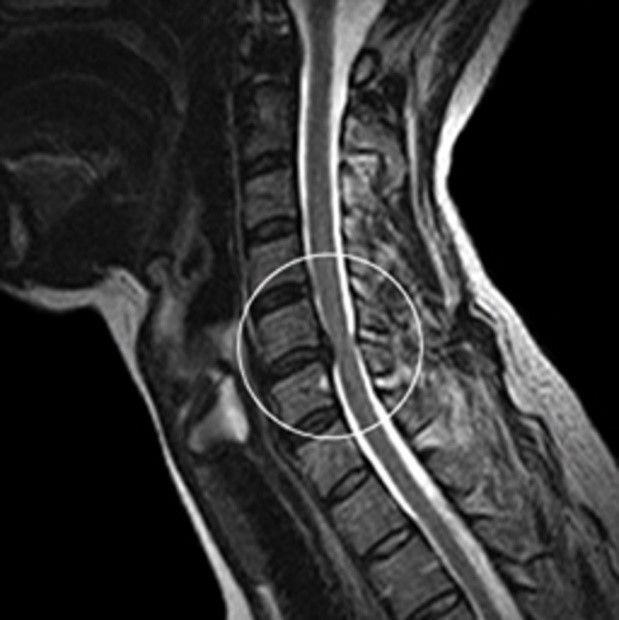

목디스크 증상 목디스크란 목 뼈 사이의 디스크가 원래의 자리에서 이탈하면서 신경을 누르거나 뼈조직이 비정상적으로 자라나 목을 지나가는 척추신경을 누르게 됨으로써 통증을 느끼는 질환입니다. 예전에는 40대 이상의 분들한테서 주로 나타나는 질환이었지만 요즘은 젊은 세대에도 흔하게 볼 수 있는 질환이 되었습니다.

목디스크가 심한 해당에는 어깨뿐만 아니라 팔과 손가락에도 저림을 동반한 고통을 느끼실 수 있다. 디스크의 수핵이 빠져나가거나 퇴행성 경추 척추증 및 경추관 협착증 등으로 척수가 눌리게 되면 대개는 팔의 힘이 빠지는 느낌을 받을 수 있다. 이러한 해당에는 팔을 머리 위로 들면 고통이 완화되는 해당이가 있는데 일시적일 뿐 목디스크의 전형적인 증상이니 꼭 정형외과에 방문하셔서 전문의에게 상담을 받아보시길 권장드린다.